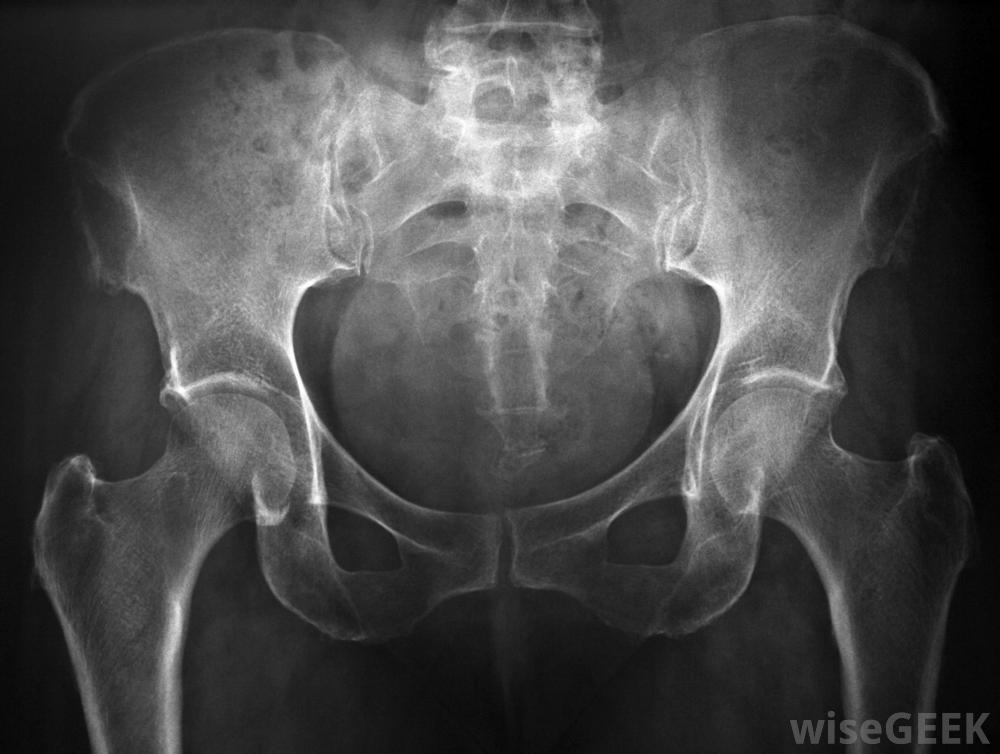

小腿珀斯病是一種髖關節退行性疾病,由于血流量不足,會嚴重影響髖關節的健康和穩定,又稱為髖關節缺血性壞死,是一種兒童期疾病,多發病,多發病接近,對這種退行性疾病的治療集中在保護髖關節不受不可修復的損傷上。常見的治療方法包括使用旨在減輕炎癥的藥物到支架和手術。X光檢查通常是用來評估髖關節的狀況和檢查骨骼的異常情況。目前還沒有明確的病因可以導致大腿-小腿-珀斯病梅奧診所聲稱,它的發展可能與二手煙暴露有關。雖然這種疾病可能會出現在兩側,也就是說它可能同時影響到兩個臀部,但它通常只發生在單側或一側在某些腿-小腿-珀斯病的病例中,使用拐杖來緩解跛行是適當的。在正常情況下,適當的循環為身體的各個部位提供充氧、營養豐富的血液在Legg-Calve-Perthes病的病例中,原本供應髖關節的血液循環受損,髖關節內缺乏血液的細胞立即開始死亡。骨細胞的死亡導致骨骼退化,使受累的骨物質受損,即使是新的,健康的細胞到達。由此導致的髖關節不穩定使其容易骨折,無法正常愈合。Legg-Calve-Perthes病可能在兒童時期的任何時候被診斷出來,但最常見的是在孩子出生后的第二年發現。疾病越早被發現,孩子的預后越好。經過全面的會診和身體檢查,通常會進行一系列的影像學檢查。經常進行骨骼掃描和X光檢查來評估兒童的狀況檢查髖關節是否有異常或骨改變。患有腿-小腿-珀斯病的兒童通常會表現出跛行并抱怨患側疼痛。限制運動范圍導致僵硬的情況并不少見一些兒童可能會說,休息或不活動關節可以減輕疼痛。久而久之,兒童跛行會導致患肢肌肉收縮。如果忽視了腿-小腿-珀斯病的癥狀或延遲治療,髖關節可能會出現永久性損傷治療Legg-Calve-Perthes病的核心是防止對髖關節的永久性損傷,抗炎藥通常用于減輕炎癥和緩解不適雖然在某些情況下使用拐杖來緩解跛行可能是適當的,但在其他情況下,可能需要使用支架固定骨骼。也可以進行手術來糾正肌肉收縮或調整髖關節Legg-Calve-Perthes病是一種影響髖關節的疾病。